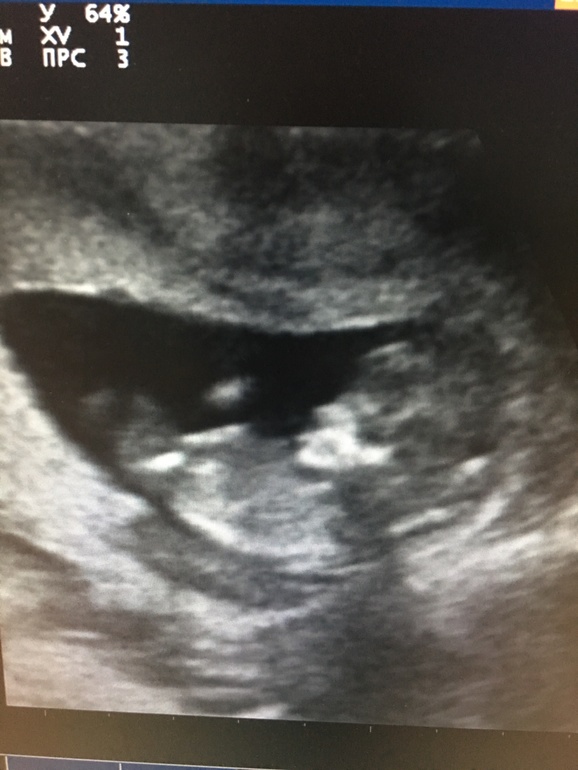

Похоже на девочку

Я бы предположила девочку. Но это из серии погадать, фото ведь "поплыло".

на фото на девочку похоже